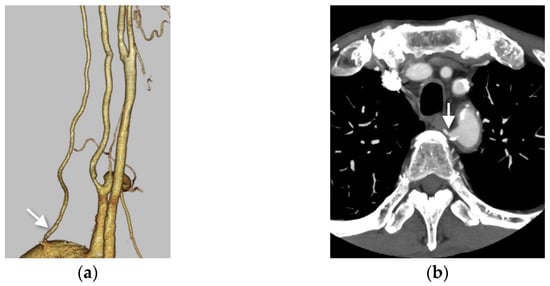

3.3. The Dual Origin of the Right Vertebral Artery